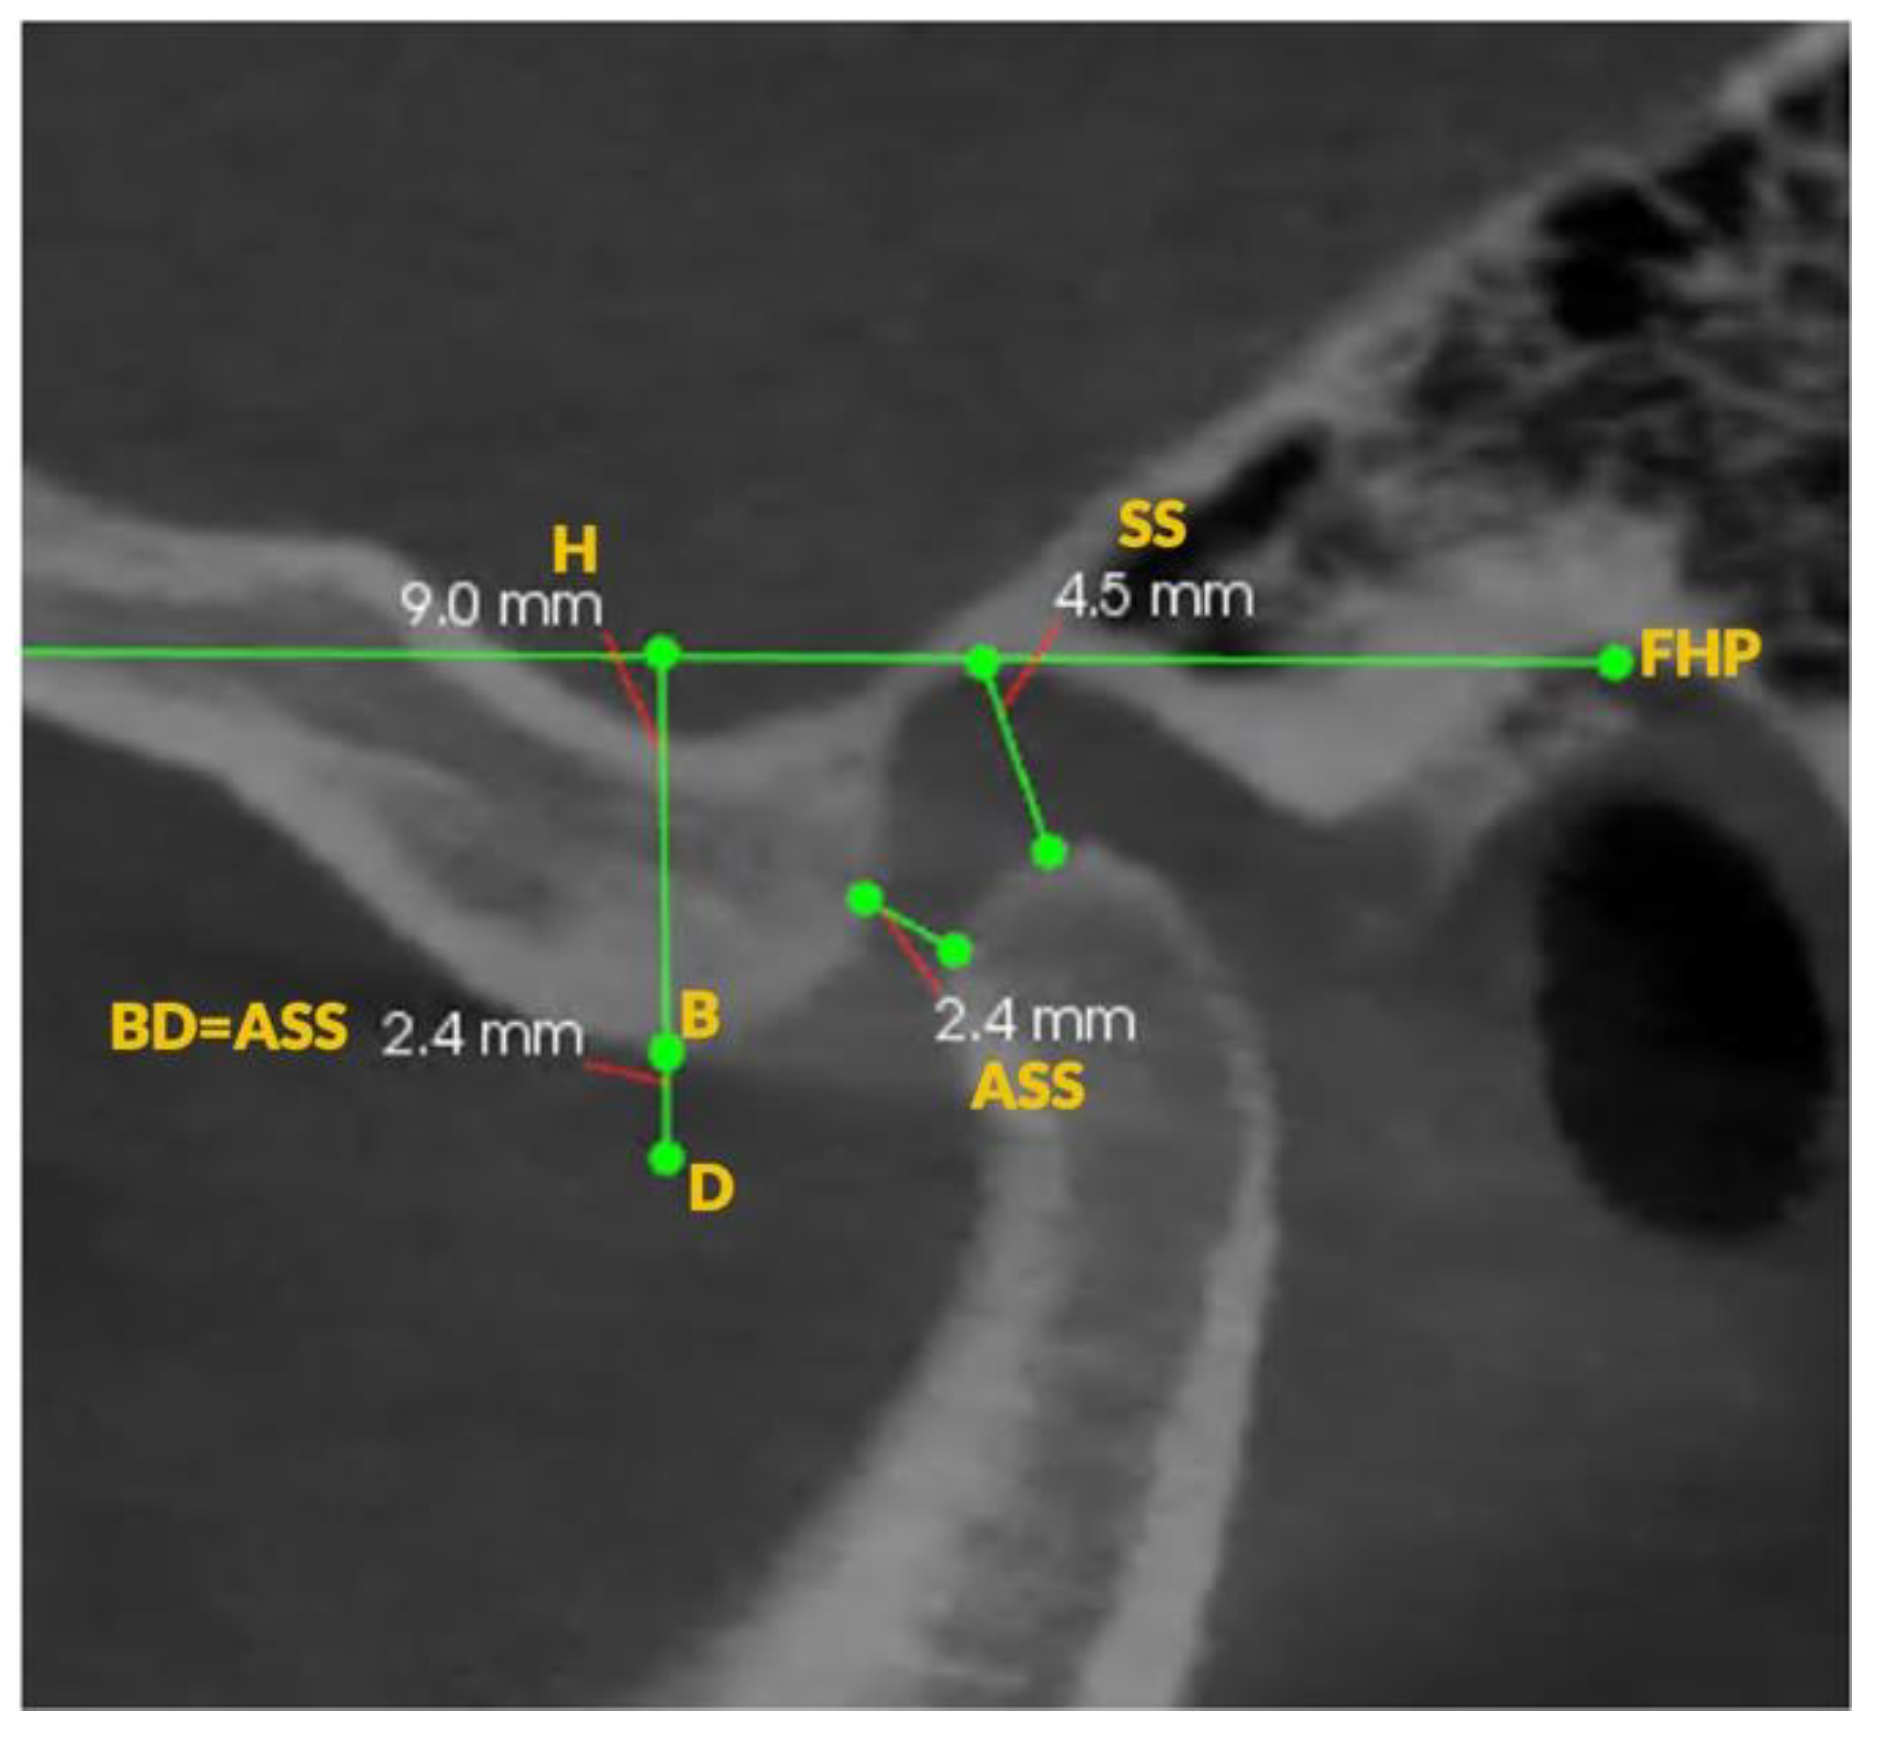

Comparison of Condylar Guidance in Opening and Protrusion Using Electronic Axiography and CBCT: An Observational Cross-Sectional Study

2. Materials and Methods